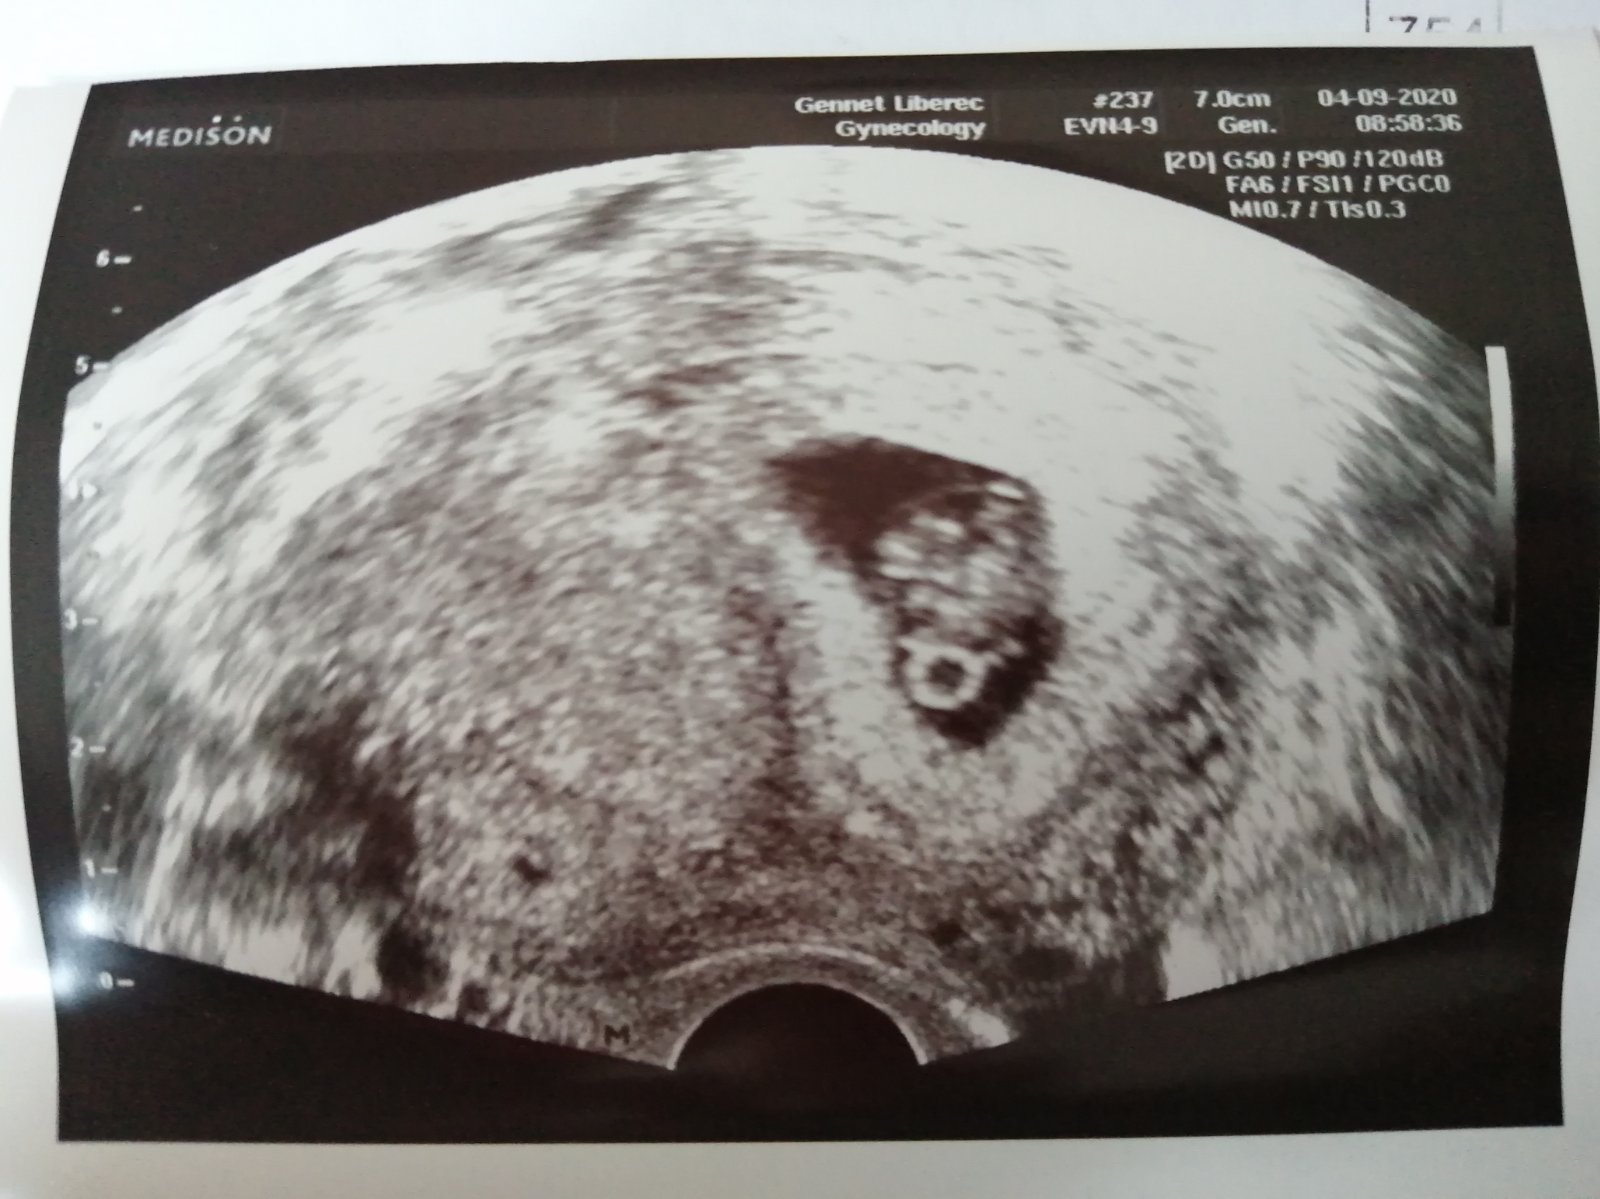

@pecenacek to bylo první na co jsem se ptala 🤣jo čekáme prej jedno viděla jsem i já Teda jen jednu srdeční činnost, ale prej můžou být za sebou a to nepozná až kolem 11tt až 13tt tak se budu pořád ptát a ujišťovat😅😁😁 Tady jsme ve své plné kráse 😍😍❤️❤️❤️🍼👶🏻

Všem Vám holky děkuji za držení Palečků. Proseděli sme 3h na pohotovosti,podle doktorky,která mi při vnitřním utz řekla,že do mě je špatně vidět,vzala to přes bricho.utz mají teda hrozný. Je tam srdíčko i fazolka 1cm.zakrvaceni zřejmě při vrtání fazolky a vytváření placenty.3h strachu.ale vše v pořádku.v pondělí do Caru. Uf 😍💞